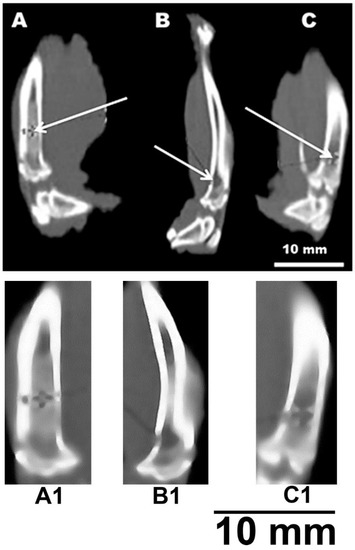

Figure 5 shows a fragment of a computed tomogram of the examined bone defects. Tomography was performed on the 80th day of the experiment. Figure 5A shows a partially consolidated fracture of the cortical bone visualized in the bone with a composite at the level of the proximal shaft. In this case, the bone density at the level of the defect is on average +674 HU (Hounsfield units) (p < 0.01). In the cavity of the intramedullary canal, a nebulous body made of a composite with an average density of +500 HU was revealed; inlet diameter up to 3 mm (p < 0.05). The defect is partially consolidated. The diameter of the bone tissue defect in the experimental group averages 2.1 mm and has a density of +344 HU at the level of the proximal diaphysis (p < 0.05). The diameter of the bone tissue defect in the positive control group averages 2.7 mm and has a density of +218 HU at the level of the proximal shaft (p < 0.05). The cancellous bone density of the positive control intramedullary canal averaged 84 HU (Figure 5B). The density of the cortical layer of the intact bone averaged +1415 HU (Figure 5C) (p < 0.05). The change in the density of the damaged bone makes it possible to determine the biocompatibility of the implant.

Figure 5.

CT image of a rat tibia defect. (A,A1)—channel with a sample; (B,B1)—channel without sample (positive control); (C,C1)—intact bone. White arrows indicate bone defects (A,B) or intact intramedullary canal (C).

It can be noted that the computed tomography data showed active processes of bone tissue regeneration in the case of using material to fill the defect compared with the control group. In densitometric analysis, the absolute density values in the area of the defect were obtained. According to the literature data, the density of the cortical layer of the intact tibia in rats, on average, is in the range of +1100–+1500 HU. The density of the intermediate zone of the regenerated tissue at the level of the proximal diaphysis is normally +300–+400 HU [23]. At the same time, a similar parameter in the experimental group averages +674 HU. This suggests that the partial consolidation and high density of bone tissue in animals of the experimental group at the level of the proximal diaphysis indicates an acceleration of the healing process of bone tissue after injury. Bone density values suggest that bone healing in the presence of the material is 30% more effective than in the positive control. This observation suggests the possibility of using the materials as a means of bone reconstruction. This also correlates with the statement that gel materials based on PVA and calcium phosphate hold great promise in the treatment of defects in supporting bone [1,7,19].